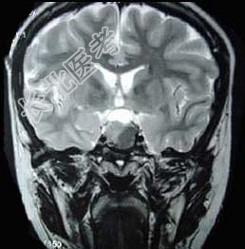

- 单项选择题男,47岁, 视物模糊数月,头痛、恶心、呕吐3天, 行MRI检查如图,最可能的诊断是 ( )

A、垂体瘤并出血

B、表皮样囊肿

C、颅咽管瘤

D、蛛网膜囊肿

E、脑膜瘤